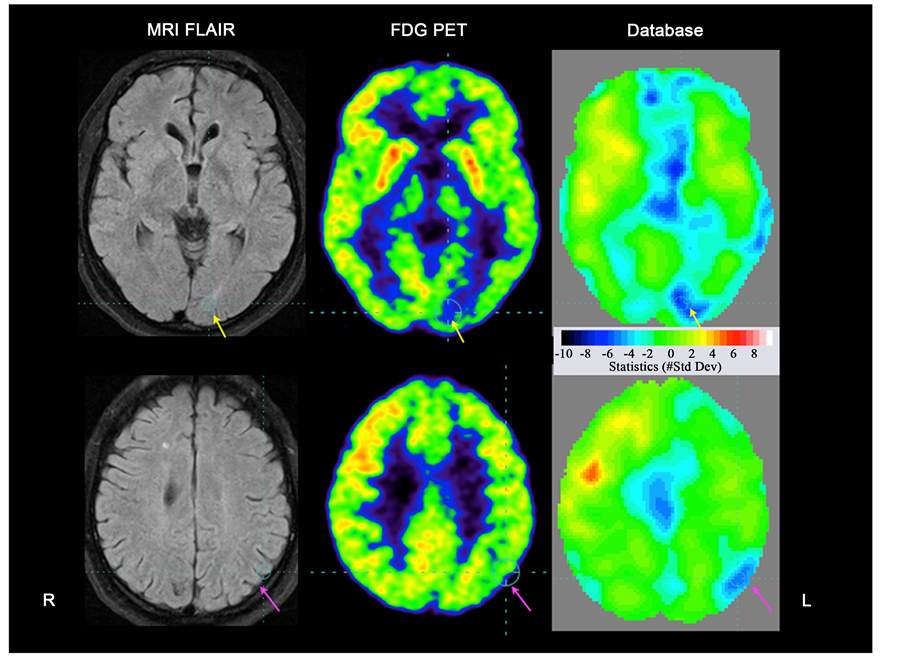

Figure 3. Two trans-axial brain imaging slices corresponding to the levels denoted in Figure 2 showing MRI FLAIR, FDG PET, and a statistical comparison of FDG PET to a database of healthy subjects. Significant metabolic reductions are seen in left hemisphere in the primary visual area close to the calcarine fissure (yellow arrow), and in the inferior parietal lobe (pink arrow). There is an impression of diffusely reduced metabolism in the whole left hemisphere, which increases the right prefrontal cortex relatively. A Z-score of <3 (p < 0.001) is considered significant.

The FDG PET scan was performed in 2013. In addition to visual analysis, a quantitative 3-dimensional stereotactic surface projection analysis (Scenium (v 3.0), Siemens) was employed that allowed direct visualization of the extent and the topography of FDG uptake abnormalities. In addition, the PET images were co-regis- tered to T1 and T2 weighted cerebral MRI scanning performed 7 months before, for identification of structural pathology and identification of anatomical structures. Significant metabolic reduction compared to a database of healthy subjects were found in the orbitofrontal cortex corresponding to treatment related damage after surgery, but also in multiple left posterior cortical areas known from extensive clinical studies and brain mapping experiments to subserve functions in the computation of visual input [6] [7] : the medial occipital region in the posterior part of the calcarine fissure, the inferior parietal lobe, and the inferior temporal lobe, starting from the occipito-temporal junction and extending into the temporal pole (Figure 2 and Figure 3). Corresponding to these areas MRI had shown no explanatory pathological signal changes.